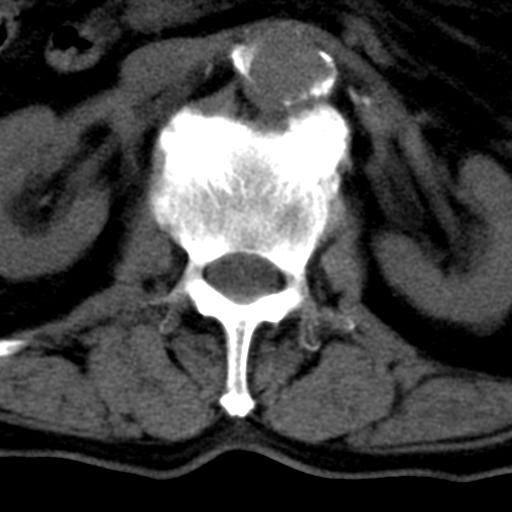

男性 82 主动脉夹层 请大家看看椎体是什么改变啊

腰椎退行性变,明显的骨赘形成,所指低密度灶为正常松质骨。